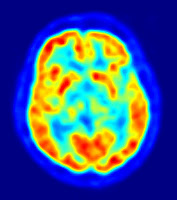

As you read this, your neurons are firing – that brain activity can now be decoded to reveal the silent words in your head

TALKING to yourself used to be a strictly private pastime. That’s no longer the case – researchers have eavesdropped on our internal monologue for the first time. The achievement is a step towards helping people who cannot physically speak communicate with the outside world.

“If you’re reading text in a newspaper or a book, you hear a voice in your own head,” says Brian Pasley at the University of California, Berkeley. “We’re trying to decode the brain activity related to that voice to create a medical prosthesis that can allow someone who is paralysed or locked in to speak.”

When you hear someone speak, sound waves activate sensory neurons in your inner ear. These neurons pass information to areas of the brain where different aspects of the sound are extracted and interpreted as words.